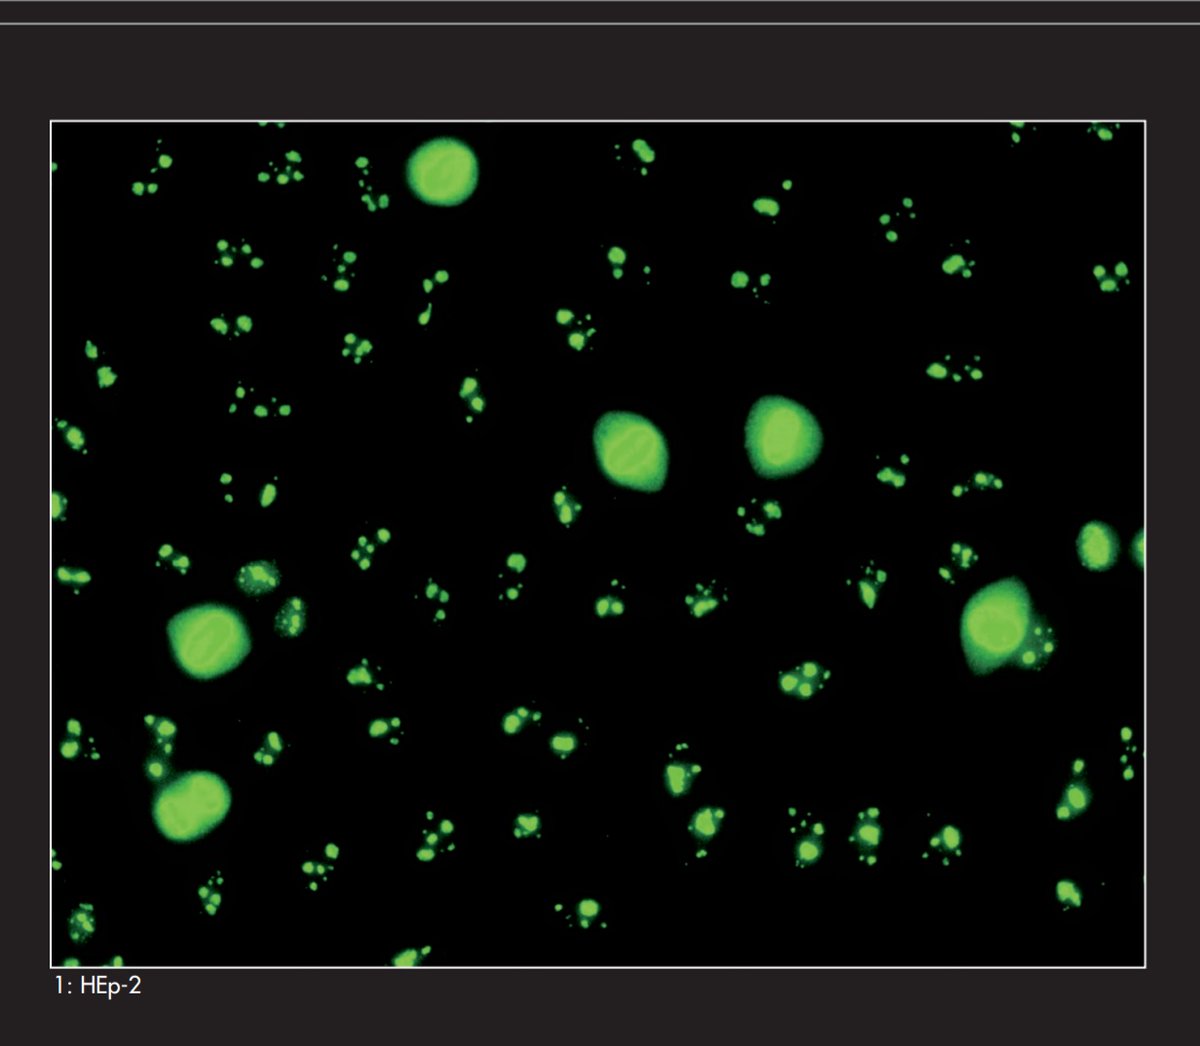

4- #centromere_pattern

وهو مرتبط بتشخيص مرض CREST

ونلاحظ وجود نقاط صغيرة ممتدة على النواة وتصل عددها الى ٩٠ نقطة مع وجود Chromosome في مرحلة Metaphase and Telophase